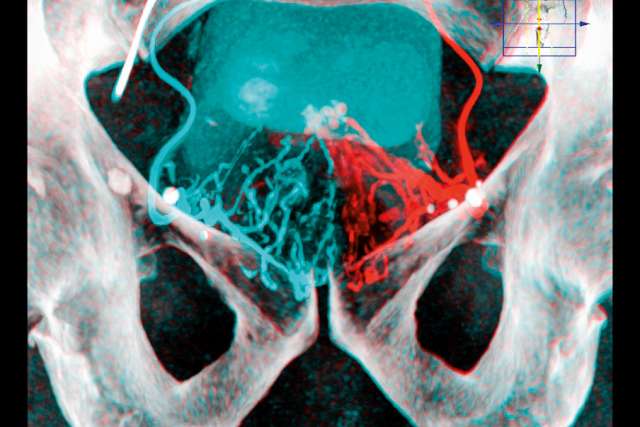

Pelvis x-ray

(Image Courtesy of Dr. Justin McWilliams)

In the PAE procedure, an interventional radiologist uses X-ray guidance to pass tiny catheters into the pelvic arteries, then performs an angiogram — an X-ray in which contrast dye is injected — to map the blood vessels and locate the ones going to the prostate. At that point, inert plastic beads are placed to block the prostate’s main blood supply. The same procedure is repeated on the opposite side, and an additional angiogram confirms that the overall objective has been achieved. Dr. McWilliams notes that PAE requires only moderate sedation or local anesthesia. Patients go home the same day and can return to their everyday activities within a week. Symptom relief generally starts within one-to-two weeks, improving progressively over the course of two months.